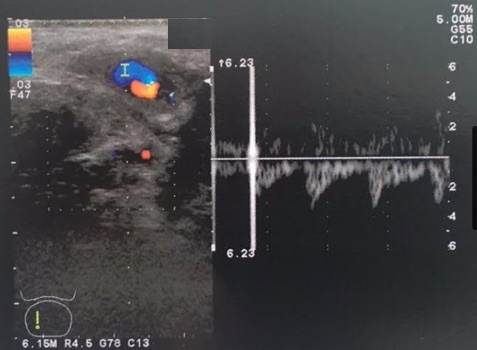

To differentiate between non-ischemic and ischemic priapism is imperative in clinical settings because the treatment of these two conditions is different and urgency of treatment too. Patient’s history and Doppler color flow ultrasound contribute to the diagnosis. However, in situations where radiological investigations are not readily available in odd hours, a clinical test described in this report, the Piesis test, may be convenient. We herein report a 10-year-old boy with non-ischemic priapism diagnosed successfully with Piesis test.Downloads